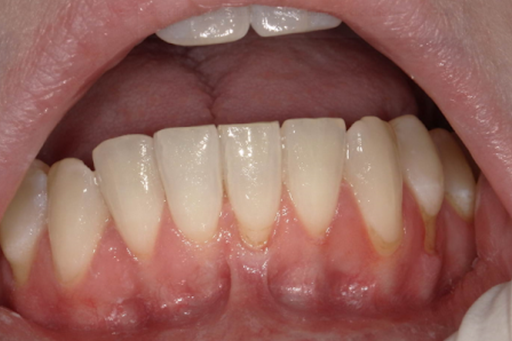

Gingival recession